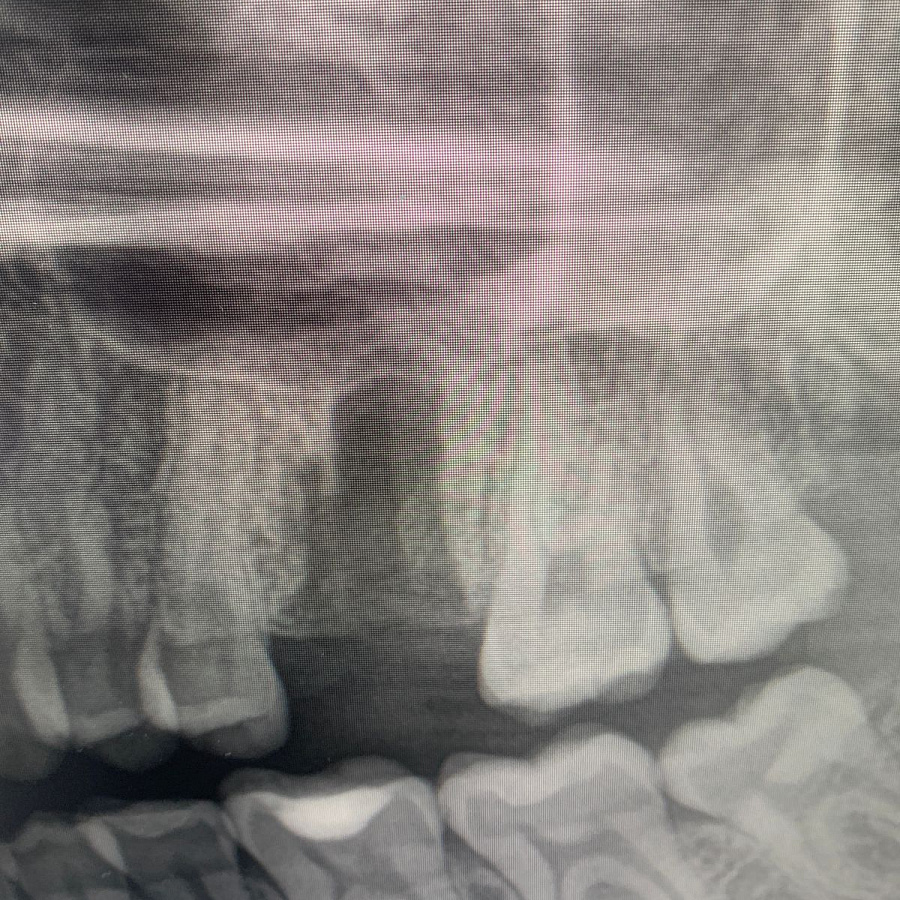

После удаления таких зубов и извлечения кисты, в кости остаётся большой дефект. Поэтому сделать одномоментную имплантацию зуба, т.е. удаление и имплантацию за один приём невозможно. В таких случаях необходимы дополнительные хирургические манипуляции по подсадке искусственной кости, чтобы сохранить объём костной ткани для последующего протезирования.

Через 6 месяцев после подсадки кости - контрольный снимок и установка зубного имплантата.

Спустя 6 месяцев пациент готов к протезированию.